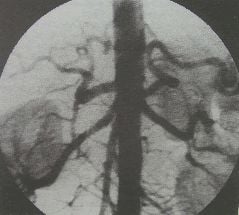

Toàn bộ quá trình này sẽ xảy ra trong phòng chụp số hóa xóa nền. Với cơ chế tương tự X-quang là cũng sử dụng tia X, hình ảnh của ống thông sẽ được liên tục quan sát trên màn hình, giúp bác sĩ điều chỉnh đường đi đến tiếp cận cũng như bóc tách lấy khối máu đông ra ngoài một cách thành công. Từ đó, dòng máu lại tiếp tục phân bố đến nhu mô não, các dấu hiệu khiếm khuyết thần kinh sẽ được cải thiện.

Tại vị trí can thiệp, bác sĩ sẽ tiến hành gây tê tại chỗ thông thường trong hầu hết các trường hợp là từ động mạch đùi, trừ khi đường vào này không làm được mới sử dụng các đường vào khác. Khi thuốc tê có tác dụng, bác sĩ sẽ chọc kim và luồn ống nong vào lòng động mạch. Dưới màn hình chụp số hóa xóa nền, bác sĩ điều chỉnh và đưa ống thông tới tận động mạch não tại vị trí có huyết khối.

Sau khi quan sát lấy được cục máu đông ra khỏi lòng mạch, cần đánh giá lại kết quả lòng mạch đã được tái thông hoàn toàn hay chưa bằng cách bơm thuốc cản quang và quan sát trên màn hình chụp số hóa xóa nền. Lòng mạch được tái thông hoàn toàn hoặc cũng có thể chưa được tái thông hoàn toàn với mức độ hẹp tồn dư cho phép không được vượt quá 30% so với đường kính lòng mạch tại cùng vị trí. Đồng thời, đoạn động mạch trước, trong và ngay sau đoạn tái thông cũng phải quan sát thấy dòng chảy lưu thông bình thường, không có dấu hiệu huyết khối hay bóc tách.